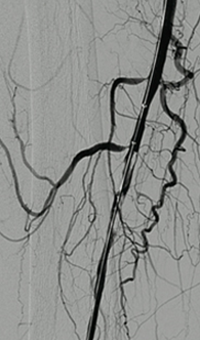

Acute DVT left lower extremity revascularization

47 year old male presented with leg swelling ~2 weeks.

Procedural steps

• Power Pulse delivery of 10mg tPA followed by

• 20 minute dwell time

• Total runtime was 300 seconds

Acute DVT Left Lower Extremity Revascularization pre-treatment angio.

Acute Iliofemoral thrombus pre-treatment

IVC Filter placed (left image)

Acute DVT Left Lower Extremity Revascularization post-treatment.

Post ZelanteDVT  pharmacomechanical thrombectomy

Case images courtesy of David Wilson M.D. – Harbin Clinic, Rome, Georgia – December 19, 2015